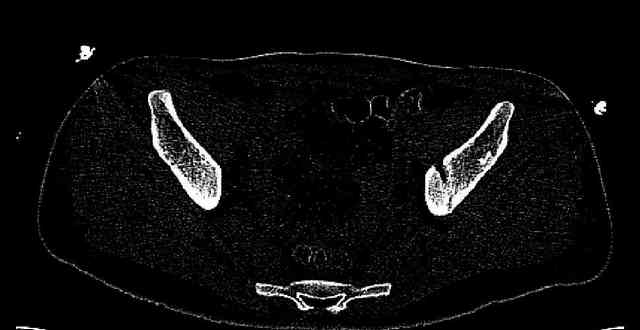

Re: Нелеченный перелом вертлужной впадины

Some more images. Does it help to guess which part of the acetabulum is displaced?